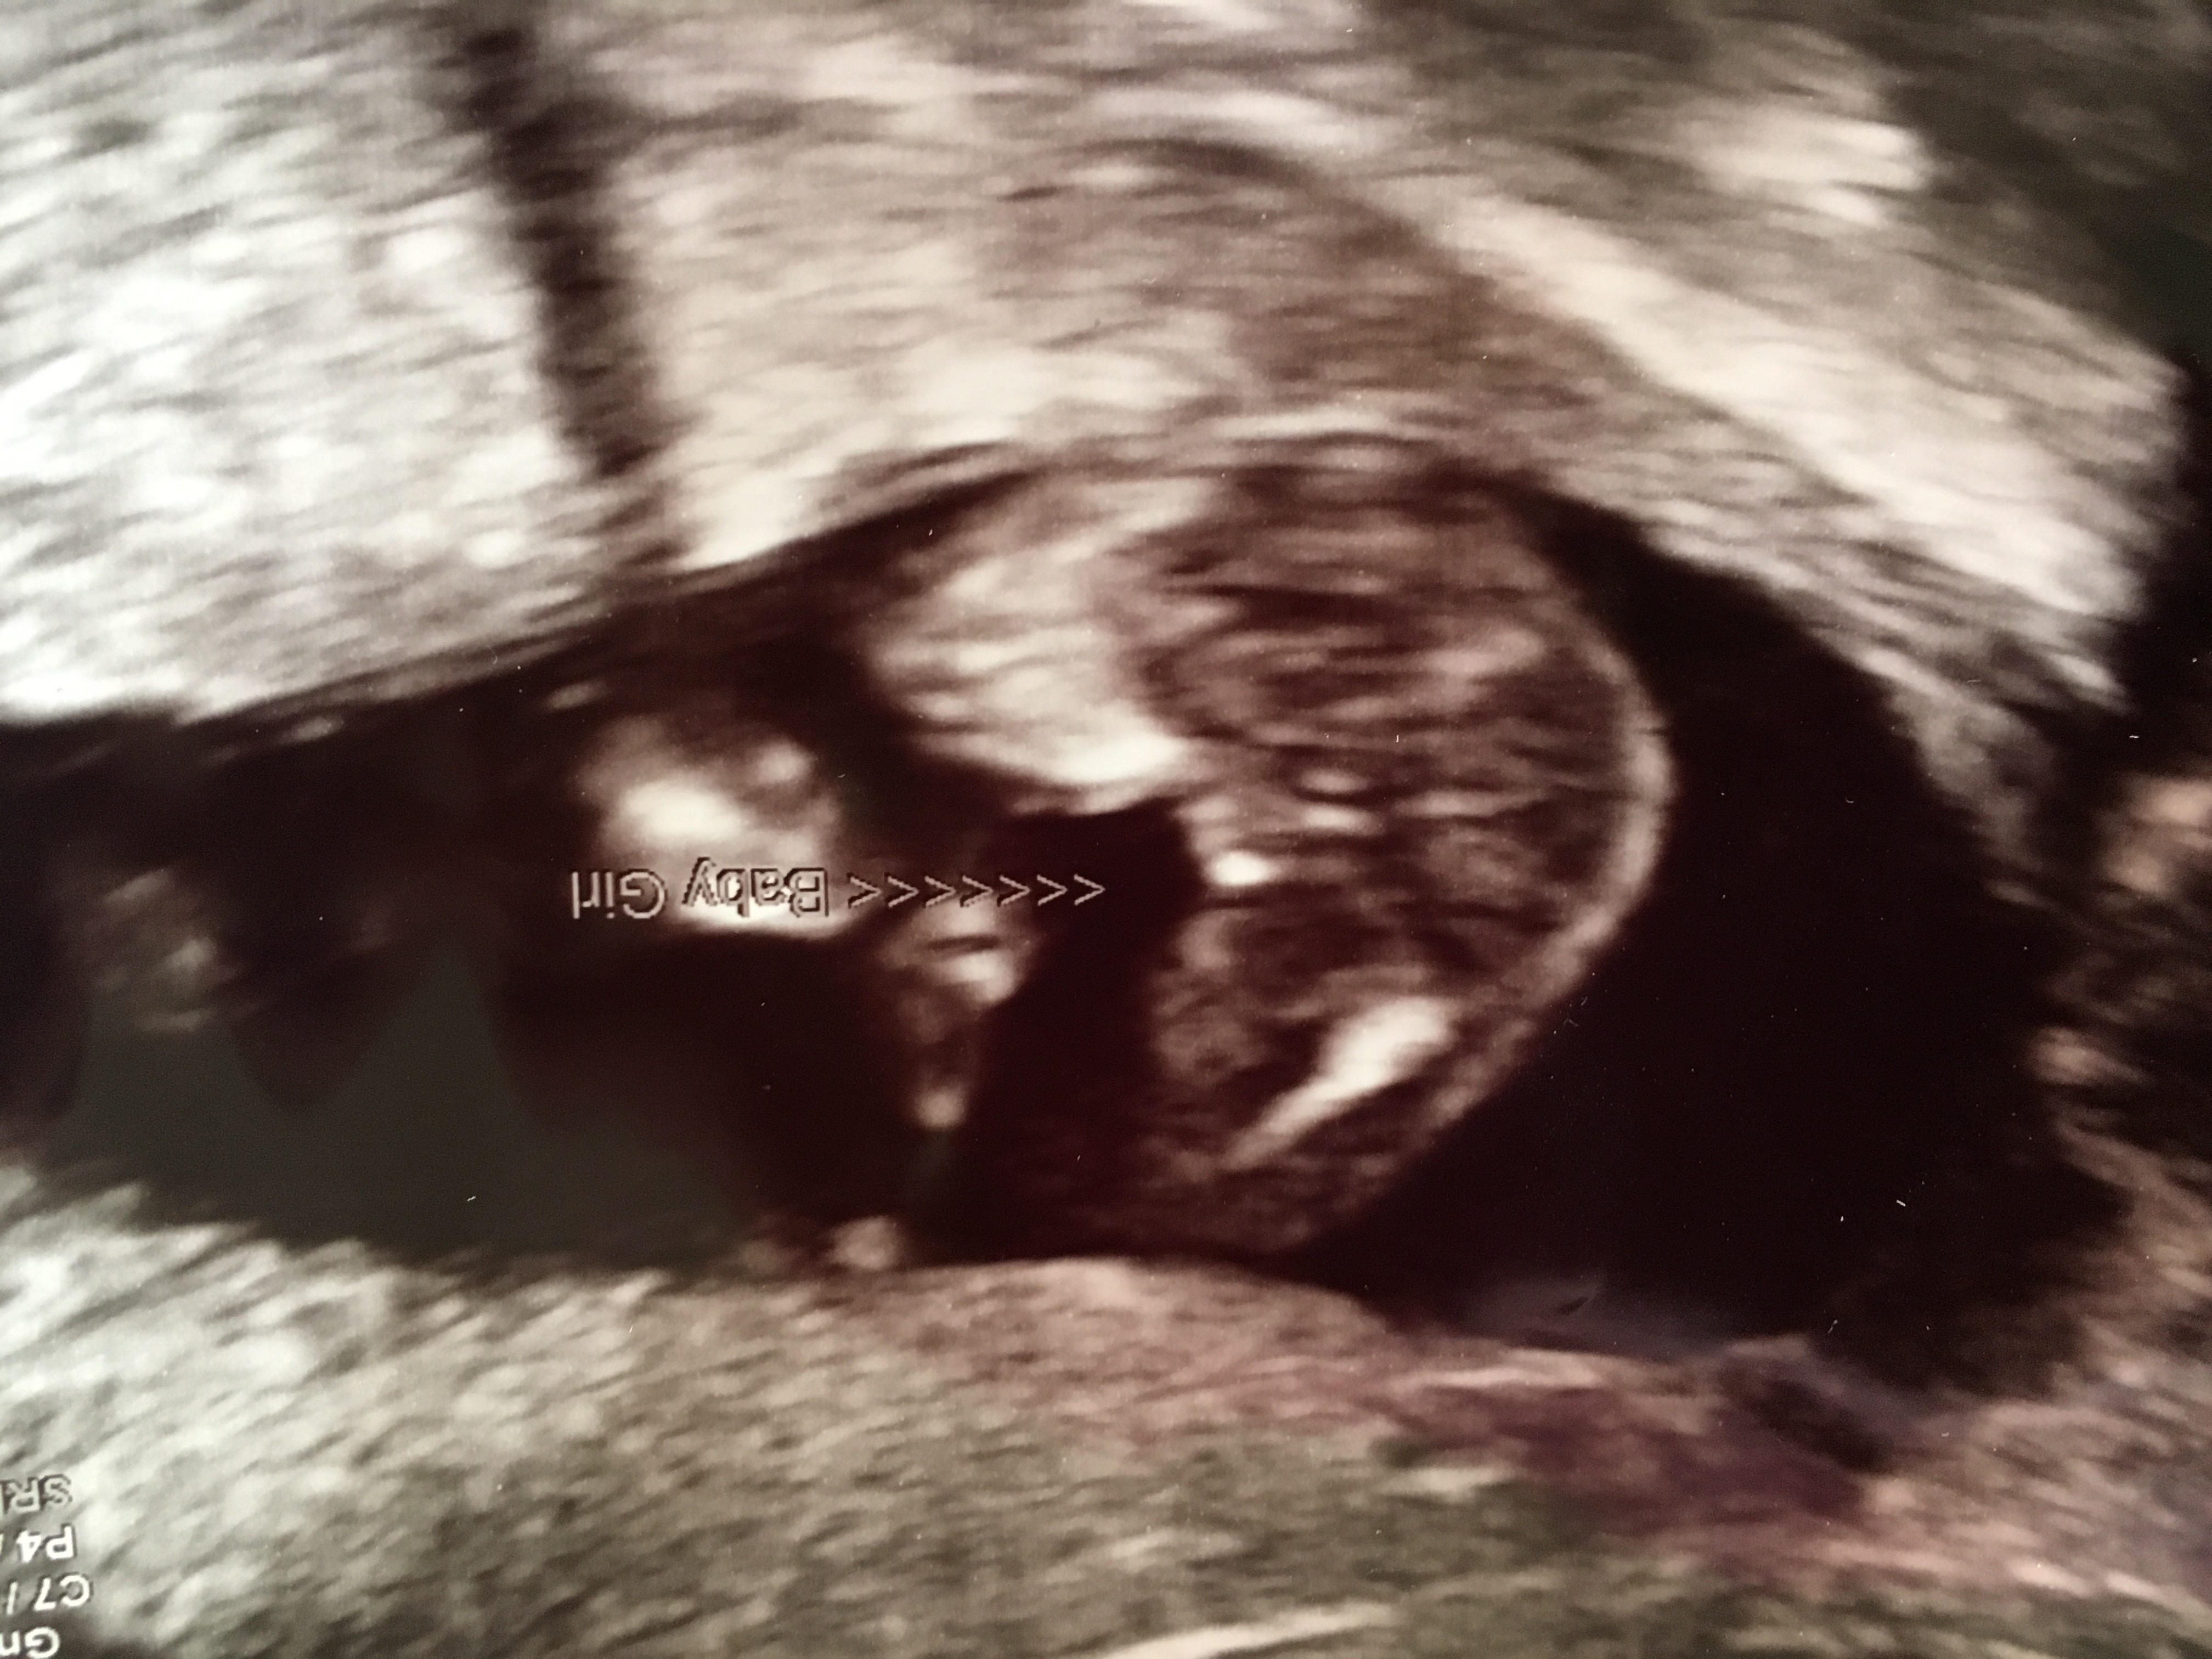

Just wondering if anyone could determine baby number 3 for me??

The sonographer said 'most likely boy' but didn't seem confident at all. I have another growth scan in 2 weeks so I'll be asking again :)

Actually I just zoomed right in I think I'm changing my guess to boy

What a bad potty shot! I would guess girl, but if the tech thinks boy then it probably is...

I think its a boy. I think i see a scrotum.

Hi. Just updating this post. My most recent scan showed what the sonographer stated as 'possible testes' but she would not confirm 100%!! Only 7 weeks until due date tho :)